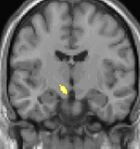

| Voxel-based morphometry shows brain area structural differences. | ||

Positron emission tomography (PET) scans indicate the brain areas which are activated during attack only, compared to pain free periods. These pictures show brain areas that are active during pain in yellow/orange color (called "pain matrix"). The area in the center (in all three views) is activated only during cluster headaches. The bottom row voxel-based morphometry shows structural brain differences between individuals with and without CH; only a portion of the hypothalamus is different.[36]